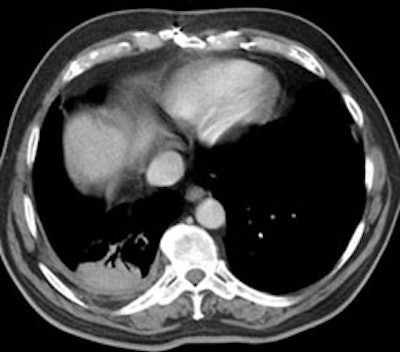

Computed Tomography: On CT the pleural thickening or calcification is clearly identified. Thickened lung markings and vessels swirl into the lesion which abuts the pleural surface ("comet tail sign"- central bronchovascular pedicle)- however, this finding may be absent in up to 8% of cases. Curvilinear air bronchograms are often visible within round atelectasis. The lesion is very commonly based or tethered by a strand to a thickened pleural surface. Pericicatril emphysema may also be seen. Volume loss within the affected lung is also common- often characterized by displacement of the fissure bounding the affected lobe. Calcification may also be found within areas of round atelectasis (up to 25% of cases)- possibly secondary to engulfment of a granuloma within the atelectatic lung, or invagination of a calcified pleural plaque. The lesion will enhance homogeneously after the administration of I.V. contrast (up to nearly 90% of cases). Inhomogeneous enhancement is atypical for rounded atelectasis [12].

Despite the ability of computed tomography to accurately identify features which are often associated with round atelectasis, it should be remembered, that the findings described above are not necessarily completely diagnostic for this entity. Other lesions can mimic these findings and rarely lung cancer can co-exist in an area of round atelectasis [12].

Round atelectasis on PET FDG imaging: The images below demonstrate the typical CT and FDG PET findings in round atelectasis. On CT, there are thickened lung markings and vessels which swirl into the lesion that abuts an area of pleural thickening. Note the lack of metabolic activity in round atelectasis on PET imaging. |